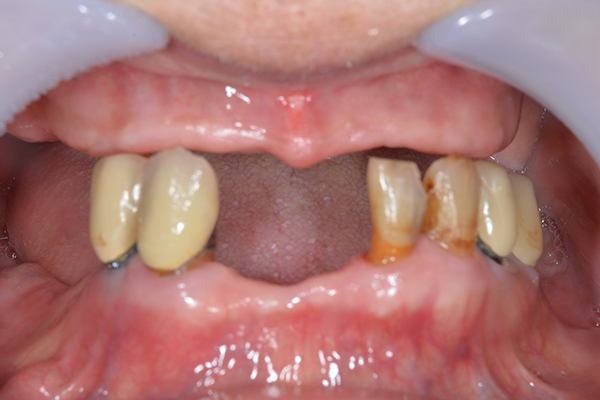

右上のインプラント周囲炎で、その部分が痛いという患者様でした。 また奥歯で噛むことが難しかったため、前歯を使用することが多くなり、 前歯が前よりも前に出てきていることも気になっていらっしゃいました。

インプラント部以外にも歯周病が進行していましたので、歯周病の治療を行いました。 残念ながらインプラントと、1本の歯が残せなかったため抜歯を行いました。 その後、前歯の出っ張りを修正することと入れ歯の安定を図るため、残っている歯を全てかぶせ物にしていくことになりました。 写真中央は抜歯後に入れた治療用の入れ歯になります。 抜歯後歯ぐきが安定しましたら、入れ歯とかぶせ物の型取りを行いました。

噛み合わせチェックでしっかり奥歯で噛めるようにし、 歯を並べます。 その後、それに合わせて前歯を作っていきます。

お口の中に入れた状態です。 非常に見た目もよい出来となりました。 バネがみえないと見栄えが全然ちがいます。